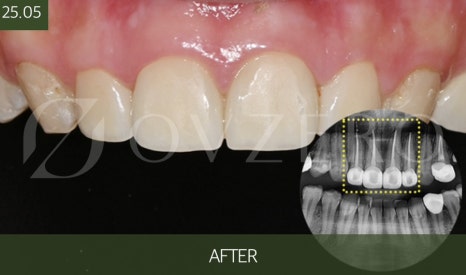

치료 과정은 어떻게 진행될까

지르코니아 크라운 치료는

생각보다 복잡하지는 않지만

각 단계가 매우 중요합니다.

처음에는

치아 상태를 확인하고

크라운 치료가 꼭 필요한지부터 판단합니다.

이후 치아를

크라운이 들어갈 만큼만 정리하고,

정밀하게 본을 떠 제작을 진행합니다.

제작 기간 동안에는

임시 치아를 장착해

일상생활에 불편함이 없도록 돕습니다.

Previous image Next image

최종 크라운이 완성되면

색과 모양, 높이를 확인하고

씹는 느낌을 여러 번 체크한 뒤 장착합니다.

이 마지막 교합 조정이

크라운 수명을 좌우하는 중요한 과정입니다.